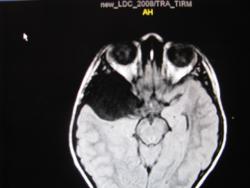

Крупная арахноидальная киста правой височной области.

да, до этого мальчик жалоб не предъявлял. наверное киста увеличилась, масс-эффект на прилежащие струкутры усилился , появилась клиника.

Да, это врожденная арахноидальная киста.